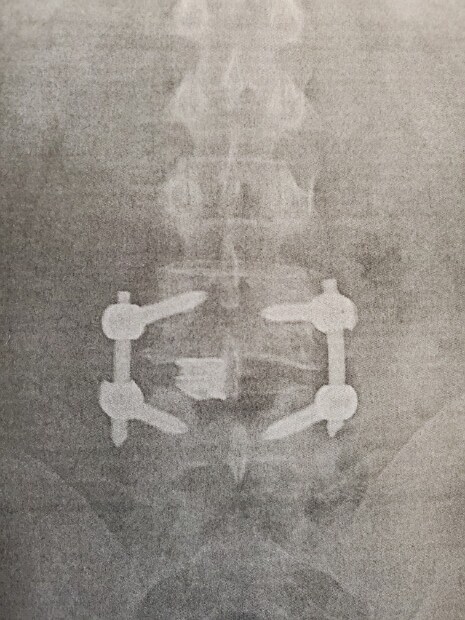

I went and saw the doctor yesterday, the fusion is taking well the recovery is going good, my L4 and L5 went from being about 35% out of alignment to back to alignment, the doctor was afraid that he might not be able to get it back to less than 15% due to how bat it was, but look at those sexy vertebrates now.

Post Image